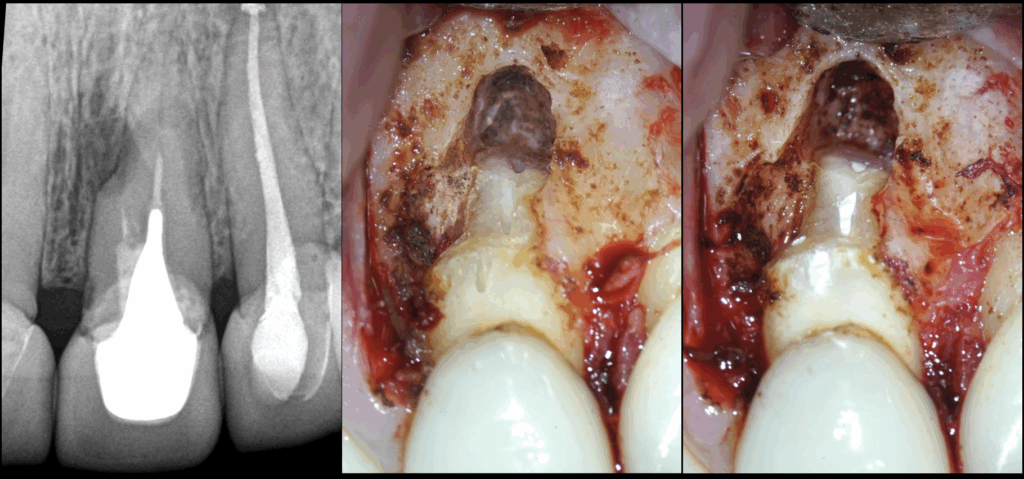

🔍 Chirurgie endodontique de 21 22

🦷 𝐋𝐚 𝟐𝟏 𝐧𝐨𝐮𝐬 𝐢𝐧𝐭𝐞́𝐫𝐞𝐬𝐬𝐞 𝐩𝐚𝐫𝐭𝐢𝐜𝐮𝐥𝐢𝐞̀𝐫𝐞𝐦𝐞𝐧𝐭 𝐢𝐜𝐢

👉 Pour sa résorption radiculaire externe

👉 Pour ses fausses routes

🔬 𝐋𝐞𝐬 𝐩𝐨𝐫𝐭𝐞𝐬 𝐝𝐞 𝐬𝐨𝐫𝐭𝐢𝐞𝐬 𝐜𝐚𝐮𝐬𝐚𝐧𝐭 𝐥𝐞𝐬 𝐫𝐞́𝐚𝐜𝐭𝐢𝐨𝐧𝐬 𝐢𝐧𝐟𝐞𝐜𝐭𝐢𝐞𝐮𝐬𝐞𝐬 / 𝐢𝐧𝐟𝐥𝐚𝐦𝐦𝐚𝐭𝐨𝐢𝐫𝐞𝐬 𝐬𝐨𝐧𝐭 𝐩𝐫𝐞́𝐩𝐚𝐫𝐞́𝐞𝐬 𝐚 𝐫𝐞𝐭𝐫𝐨 𝐞𝐭 𝐨𝐛𝐭𝐮𝐫𝐞́𝐞𝐬 𝐚𝐮 𝐜𝐢𝐦𝐞𝐧𝐭 𝐛𝐢𝐨𝐜𝐞́𝐫𝐚𝐦𝐢𝐪𝐮𝐞.